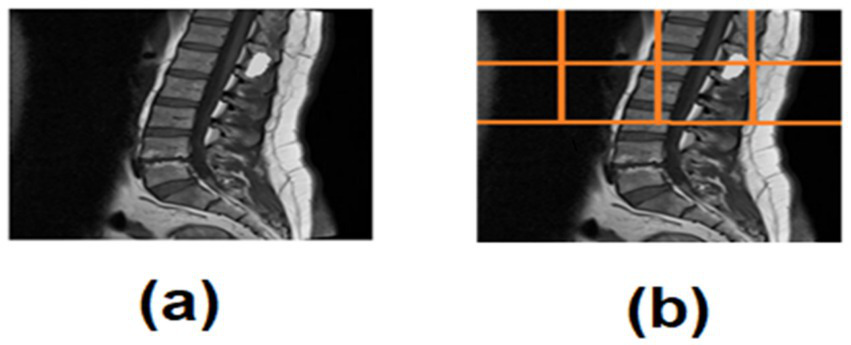

A semi-automated quadrant-based ROI detector was used to localize the spinal cord region:

-

The axial slice was divided into four quadrants.

Left–right quadrant similarity metrics (mean intensity) identified the spinal midline.

The non-relevant quadrants were recursively subdivided into two sub-quadrants.

The sub-quadrant with the highest midline-proximal intensity was selected as the ROI.

This method prevents over-segmentation and ensures consistent localization even in non-centered scans (Figure 2).

Figure 2

(a) Spinal tumor MRI, (b) ROI quadrant analysis of spinal tumor MRI.